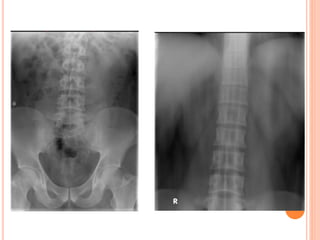

 The preliminary kidney,

ureter, bladder (KUB)

radiograph is an

indispensable part of

the sequence.

PLAIN RADIOGRAPHY(UTP)

- from the suprarenal

region to a level below

the symphysis pubis.

- The patient should void

immediately prior to

examination.

- may require additional

images

KUB

 Additional views:

- Oblique conventional

radiographs.

- Nephrotomogram.

- Open bladder film.

KUB ANALYSIS

 Musculoskeletal: evaluate all bone elements.

 Psoas muscle margin: straight, convex or absent.

 Intestinal gas: overlap, displaced.

 Kidneys

 Calcifications: overlying the UT or outside.

 Gas shadow: abnormal air at UT.